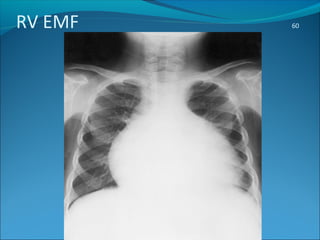

CXR

On chest radiographs,esp. in RVEMF the heart is always

enlarged in the transverse diameter, and often it is enormous.

This may be due to a coexisting pericardial effusion, but is

usually due to a dilated, almost aneurysmal right atrium.

 If pericardial fluid is scanty there will be an outflow tract

convexity, which on fluoroscopy or ultrasound is seen to be

very active.

In late cases there may be an oblique, linear calcification at the

elevated apex of the right ventricle or base of the pulmonary

conus .



The lung fields are strikingly oligemic and, because of low

cardiac output, the superior vena cava and azygos veins are

very prominent.

In LV EMF , myocardial calcification and pulmonary congestion

may be seen with a moderate cardiomegaly

RV EMF 60